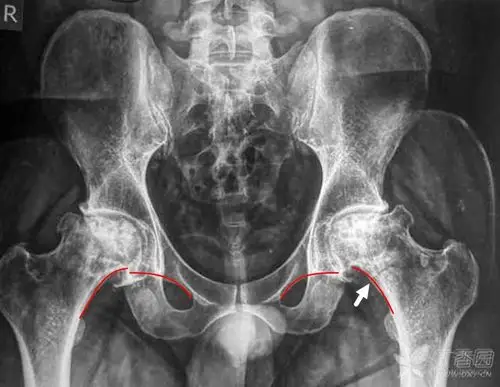

提示存在着髋关节轻度的半脱位.